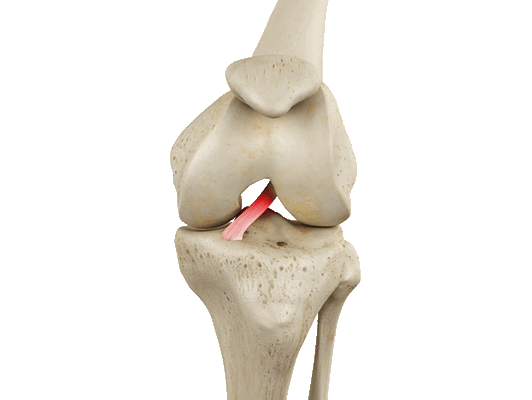

Как выполняют пластику передней крестообразной связки (ПКС) коленного сустава

Передняя крестообразная связка отвечает за динамическую устойчивость коленного сустава, фиксируя голень от нефизиологического смещения кпереди и поддерживая наружный мыщелок большой берцовой кости. Более 1/2 стабильности коленного отдела обеспечивается благодаря ПКС. Именно поэтому данную структуру специалисты называют первым стабилизатором колена, без нее сустав нормально работать не сможет. Располагается она в самом центре костного соединения, перекрещиваясь с задней крестообразной связкой х-образно, что и дало этим двум структурным элементам одноименные названия. Мы же будем говорить сейчас конкретно о ПКС и посттравматической реконструктивно-пластической ее коррекции.

Как травма выглядит на МРТ.